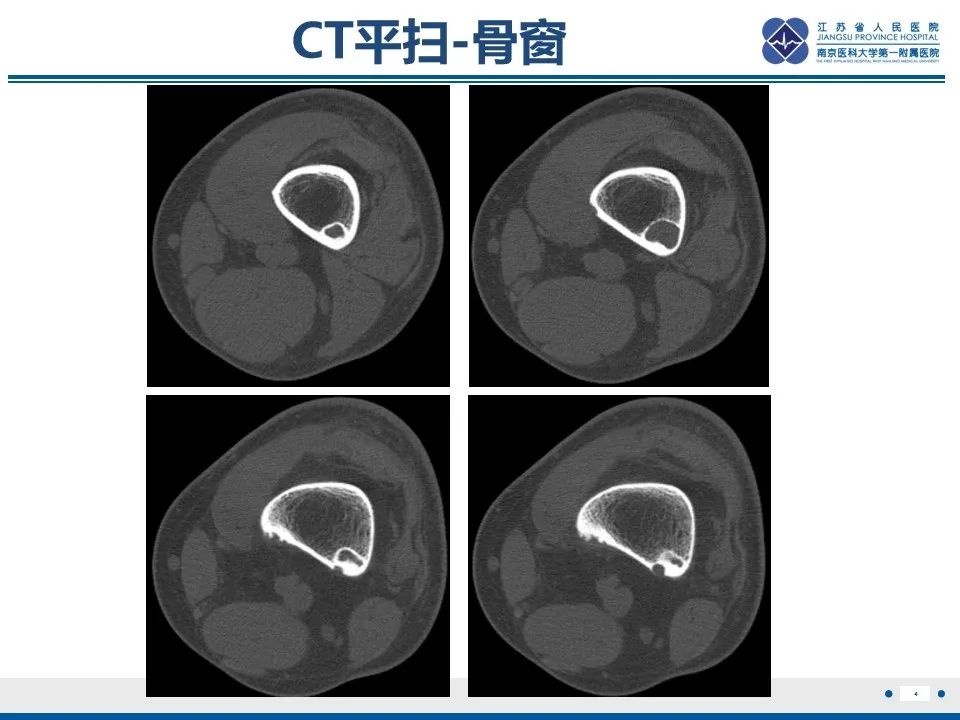

非骨化性纤维瘤影像表现与鉴别